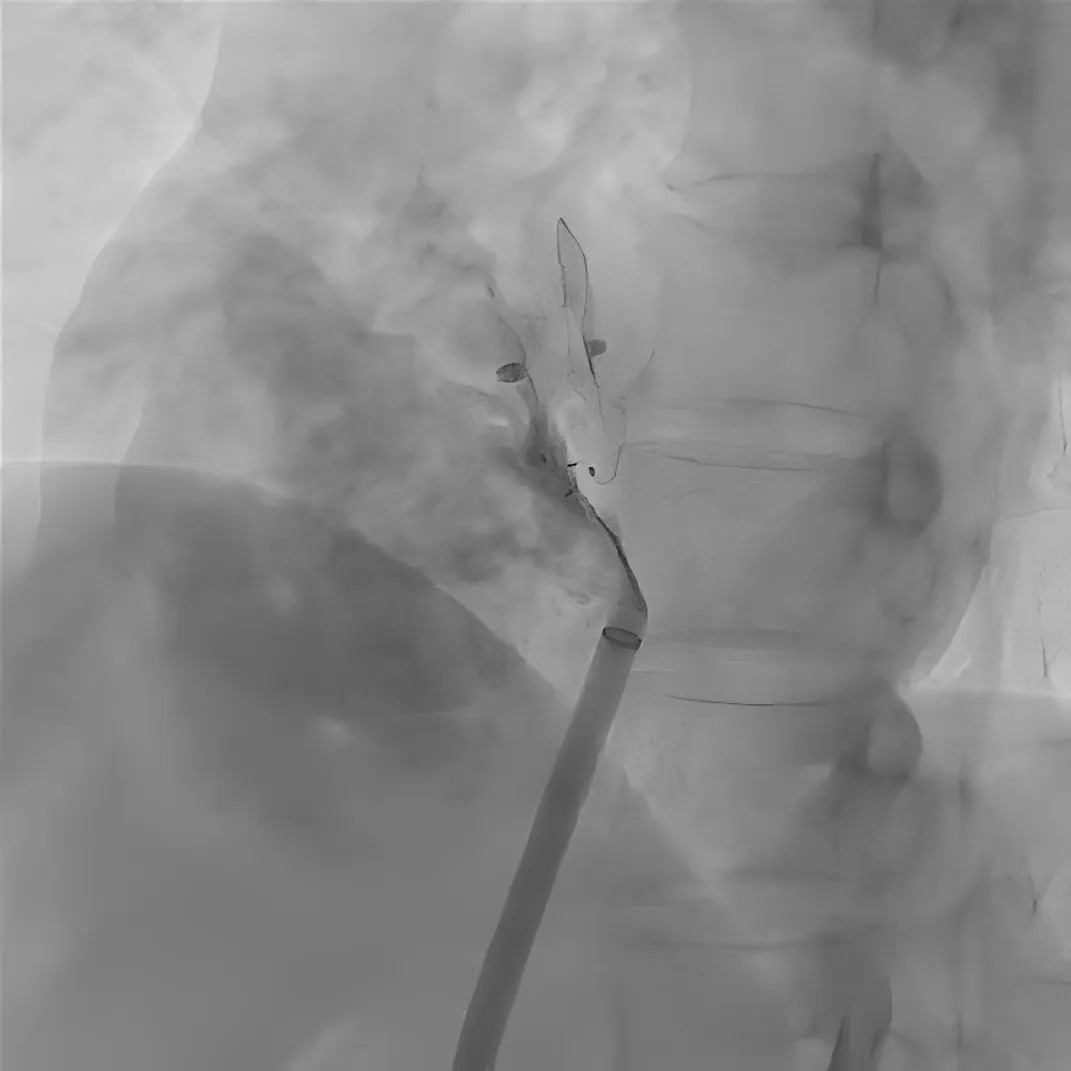

图3 导丝及导管经残余分流处进入左心房

图4 使用可降解封堵器成功封堵残余分流

四个Mark显示了可降解卵圆孔未闭封堵器的位置